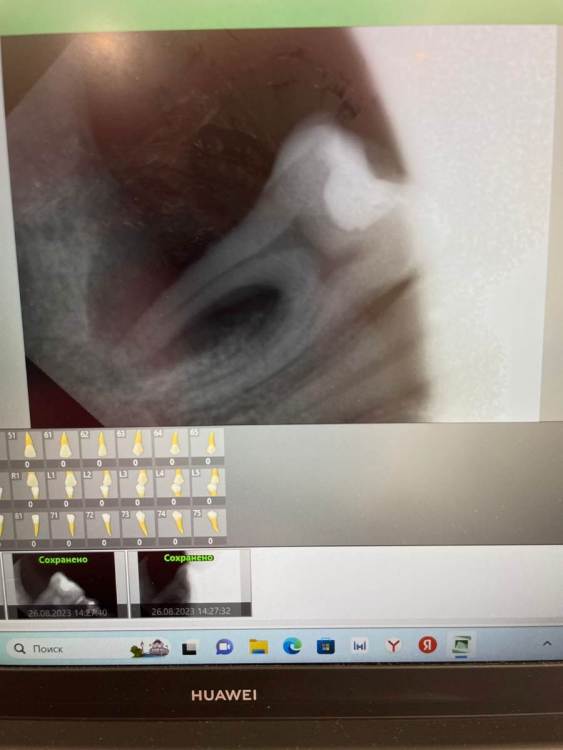

Graf Опубликовано 26 августа, 2023 Поделиться Опубликовано 26 августа, 2023 Пациентка пришла с жалобами на пульсирующие боли и небольшую опухлость в области 46 зуба. Что можете сказать по данному случаю и есть ли возможность сохранить этот зуб? Ссылка на комментарий